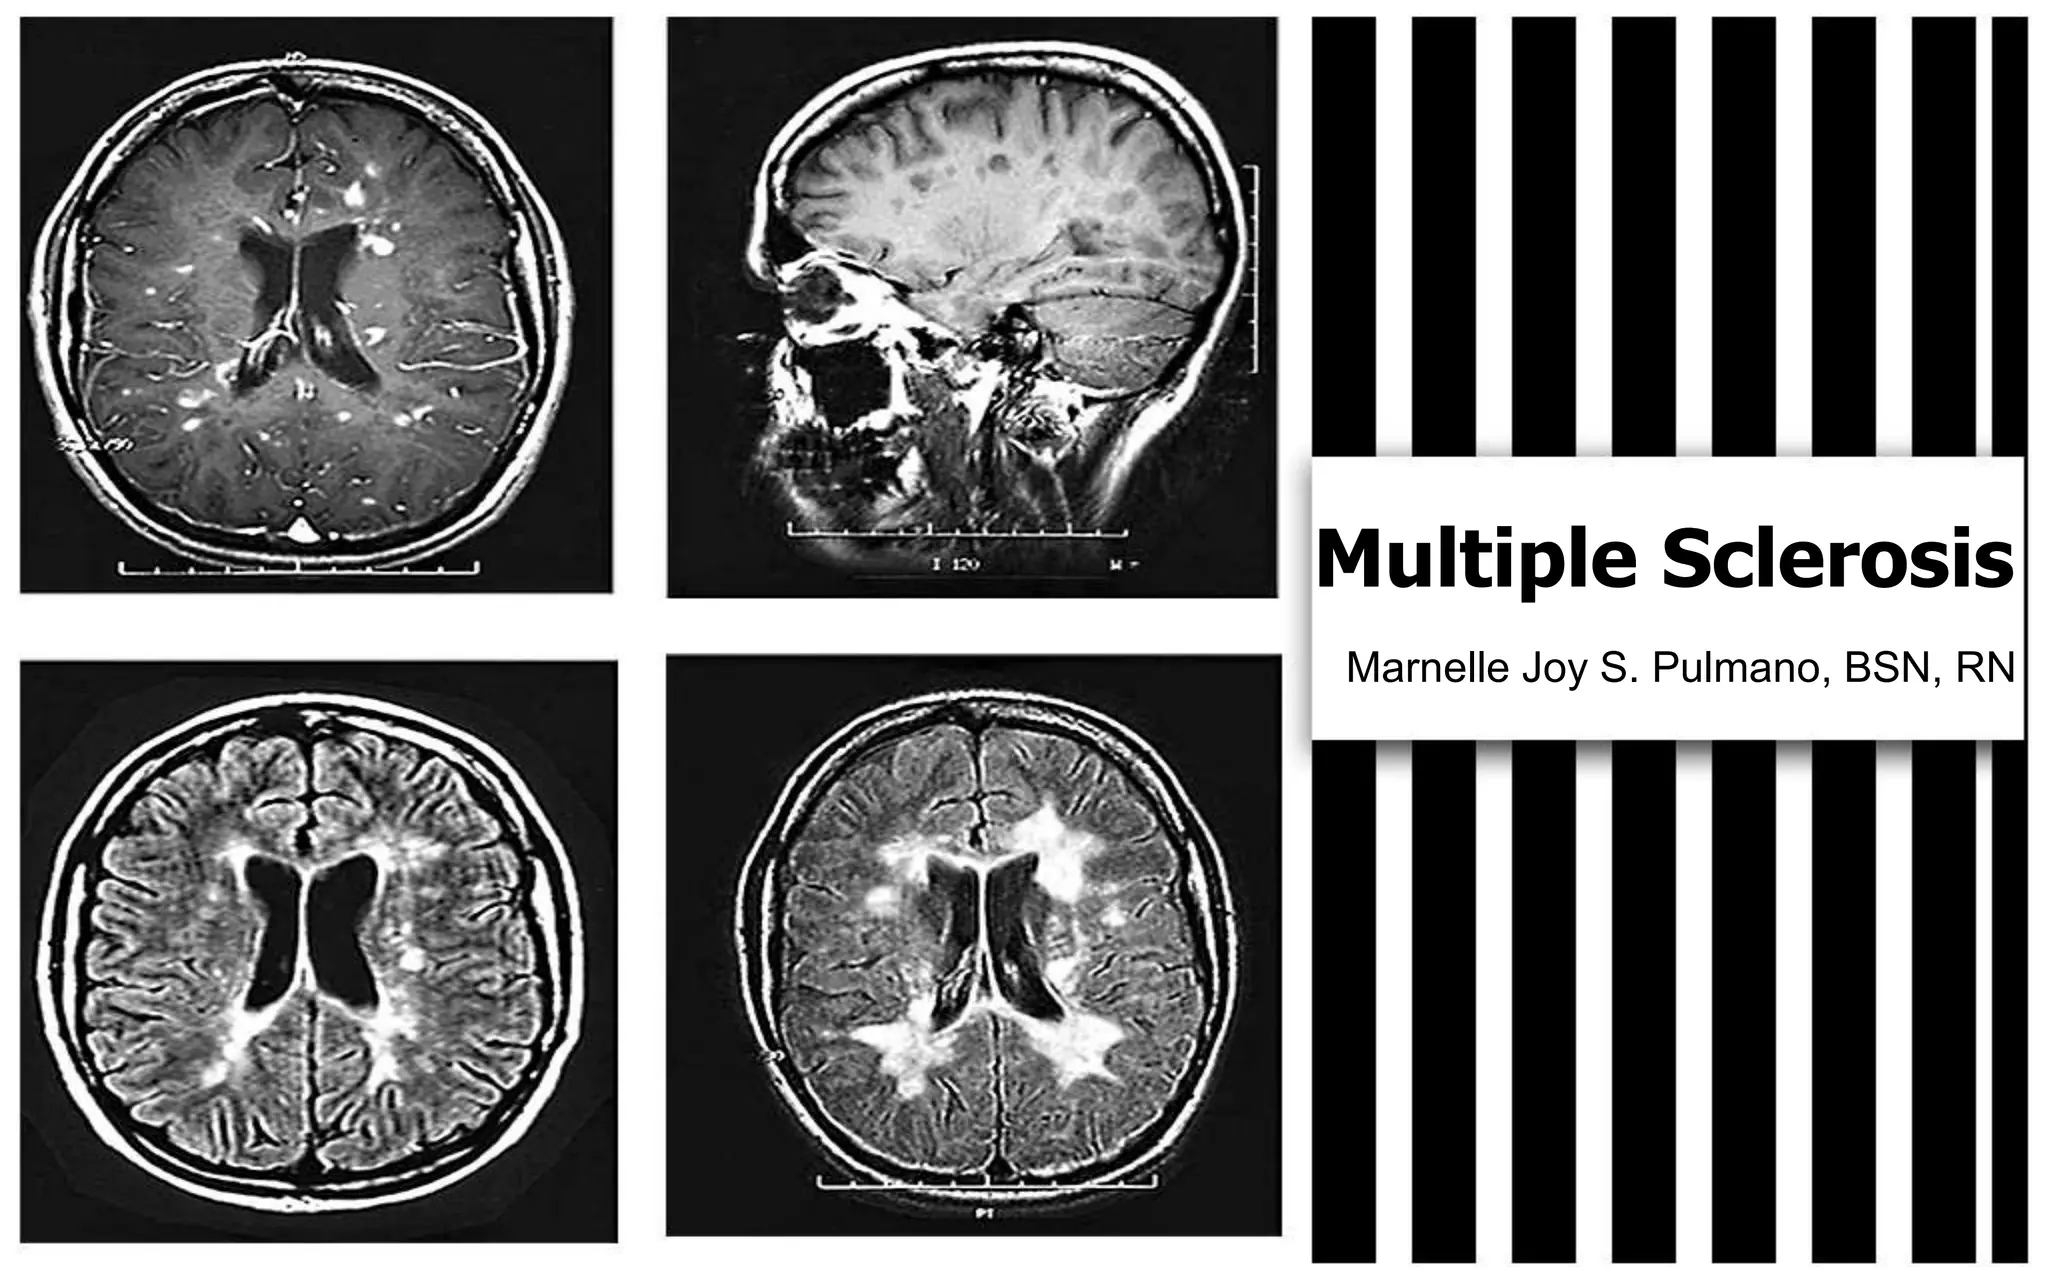

Multiple Sclerosis is a chronic and progressive disorder that affects the brain and spinal cord. It is caused by damage to the myelin sheath, which leads to scarring and decreased nerve conduction. It most commonly occurs in people between 20-40 years old, affects 1 in 1000 people, and is possibly an autoimmune disorder or viral exposure. Symptoms include weakness, impaired vision, fatigue, and loss of coordination. Treatment focuses on controlling symptoms, preserving function, and maximizing quality of life through exercise, nutrition, medication management, and therapy.